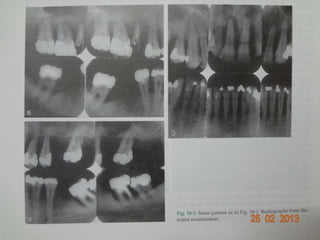

 Radiographic evidence of bone loss.

Clinical diagnosis  Detectionof chronic inflammatory changes in the marginal gingiva,  Presence of periodontal pockets,  Loss of clinical attachment,  Radiographic evidence of bone loss.